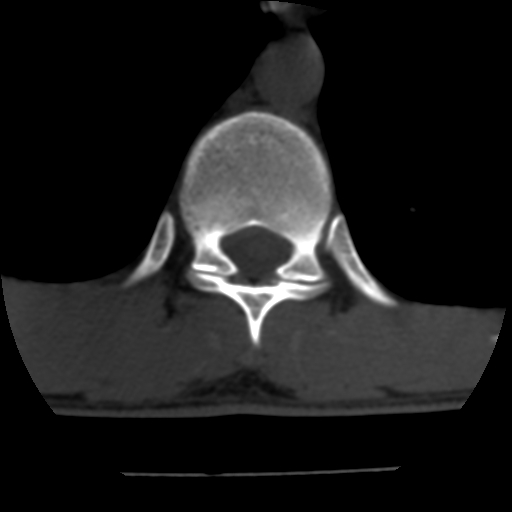

男,31岁,从6米高处坠落伤两天,腰背部疼痛,临床要求ct扫描胸10-腰1。请大家帮忙看看骨质有问题吗?

t12、l1锥体前缘轻度楔形变,平扫示椎体前缘骨小梁欠规整,第9幅图示椎体前缘骨质不连续,结合外伤史考虑椎体轻度压缩骨折。

楼主扫描层厚可能较大,每个椎体只有三个层面.

从所示层面分析,无明确骨折征象,象类似病人我个人会建议mri除外骨挫伤.

从上查骨窗第九片椎体前缘皮质显示断裂.压缩骨折?